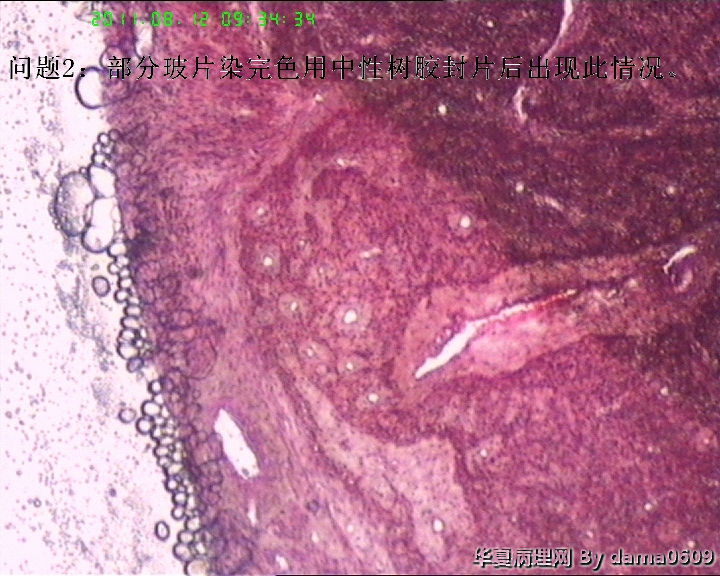

老师好!以前学生也遇到过此情况,偶尔染出的片子的细胞核的上方会出现黑色的异物,多见于子宫平滑肌瘤的片子。很影响观察核的形态、核分裂像。初以为是苏木素杂质,而且不经常出现,所以没在意。最近此现象很严重,许多的片子都出现此情况,反复过滤苏木素不见好转,新配苏木素也是如此。经过仔细观察,现发现似乎不是杂质,是细胞核上方覆盖着小气泡(如图),不知何故,如何解决??另外一个问题,我们的片子封片后经常出现斑片状或整张片子模糊,似乎树胶没有封到(如图),不只是脱蜡不干净,还是脱水出问题?此想象并不是出现在所有的一批片子上,而是个别。请老师们帮助指点。谢谢。

因为不知道你的脱水、染色程序,所以,只能推测性的回答你的问题了(如有不对的的地方,请指教)。细胞核的上方会出现黑色的异物从第图5、6、7、8、9中可以中看的很清楚,看着不像是苏木素结晶,从平滑肌细胞核上看着有的细胞有些像苏木素深染了(有几个细胞核染的类似图5、6、7、8、9中的,这几个肯定不是深染),是有什么东西覆盖在细胞核上,我觉得应该是苏木素-伊红以后的问题(封片过程中脱水透明不彻底造成的,如果是干封,酒精中的水分带带二甲苯中,透明后,吹干在封片后,有可能出现这种情况,湿封也是一样,封片后,玻片的组织上出现小的水泡,可能出现这种情况。你试试把脱水透明的无水酒精和二甲苯换了看看);封片后经常出现斑片状或整张片子模糊,似乎树胶没有封到,从图10来看很明显是我刚才提到的,是脱水不好(无水酒精不纯,而把水份带到二甲苯中),封片后就出现这种情况了(这个不是气泡),后面的图13、14怎么看着像没封片一样(应该不会是胶的问题吧?)你先换换酒精和二甲苯试试!